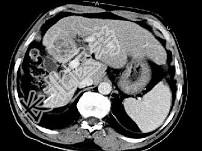

- 单项选择题女性患者,56岁, 腹胀、双下肢浮肿、乏力、食欲不振,影像所见如下图, 最佳的诊断是 ( )

A、肝炎后肝硬化并肝癌

B、局限性脂肪肝

C、原发性肝癌

D、血吸虫肝硬化并肝癌

E、酒精性肝硬化并肝血管瘤